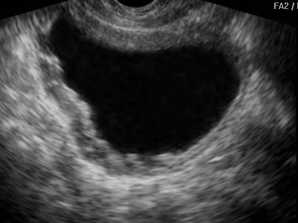

Ультразвуковой признак острого цистита - наличие в полости мочевого пузыря мелких гиперэхогенных частиц. Это так называемый «осадок», который состоит из скоплений эпителиальных клеток, эритроцитов, лейкоцитов и некротических тканей. Возможно утолщение стенок органа более 3 мм, но в целом их контуры ровные и без деформаций. В случае перехода болезни в хроническую форму стенки могут деформироваться, форма мочевого пузыря нередко изменяется, он становится асимметричным. В полости также присутствует осадок в виде гиперэхогенных (светлых на картинке) сгустков. Размер органа несколько уменьшается, что говорит о фиброзных изменениях стенок вследствие длительного воспаления.

- эхонегативная структура (на экране отображается темным цветом);

- орган внутри полый, различные включения отсутствуют;